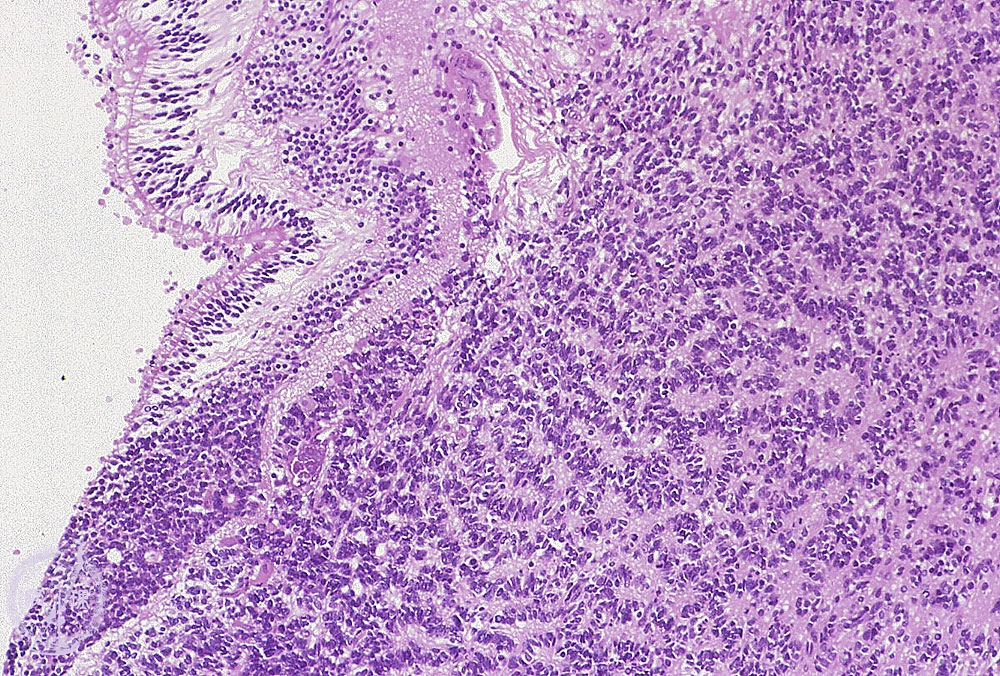

- ★(10)Retinoblastoma

Microscopic view (H&E, low power) A white mass arises from the retina (arrows), was composed of hyperchromatic small round cells with high N/C ratio (Circle). Flexner-Wintersteiner Rosettes are seen.